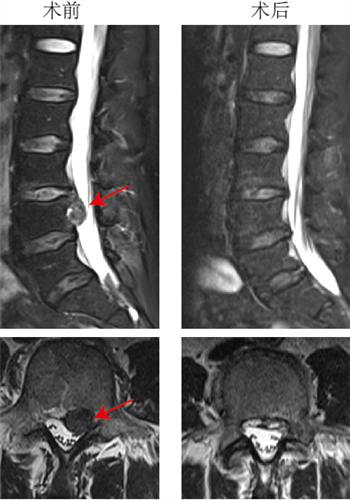

结合樊先生核磁共振(MRI)等相关的检查结果,医生发现樊先生的腰3/4节段左侧椎间盘巨大突出,并脱出游离至腰4椎体后缘,将脊髓神经严重挤推至右侧,这也是造成樊先生明显的腰腿痛的原因。针对这种高度游离脱出的腰椎间盘突出症,以往常采用椎板部分切除、甚至腰椎融合术,手术创伤大、风险高、费用高。重医附二院楚磊教授、石磊医师、于庆帅医师及护理团队进行了缜密的讨论与研究,和樊先生详细沟通后,决定行经皮内镜手术来治疗他的腰椎间盘突出症。

正是在如此强大的技术支撑之下,樊先生的手术顺利进行。术中,医生精确定位患者腰椎病灶节段,只通过皮肤不足1cm的切口,在椎弓根开了一个小孔,将脱出压迫神经的髓核组织成功摘除。

术前术后对比,及术中椎体环锯成形术影像